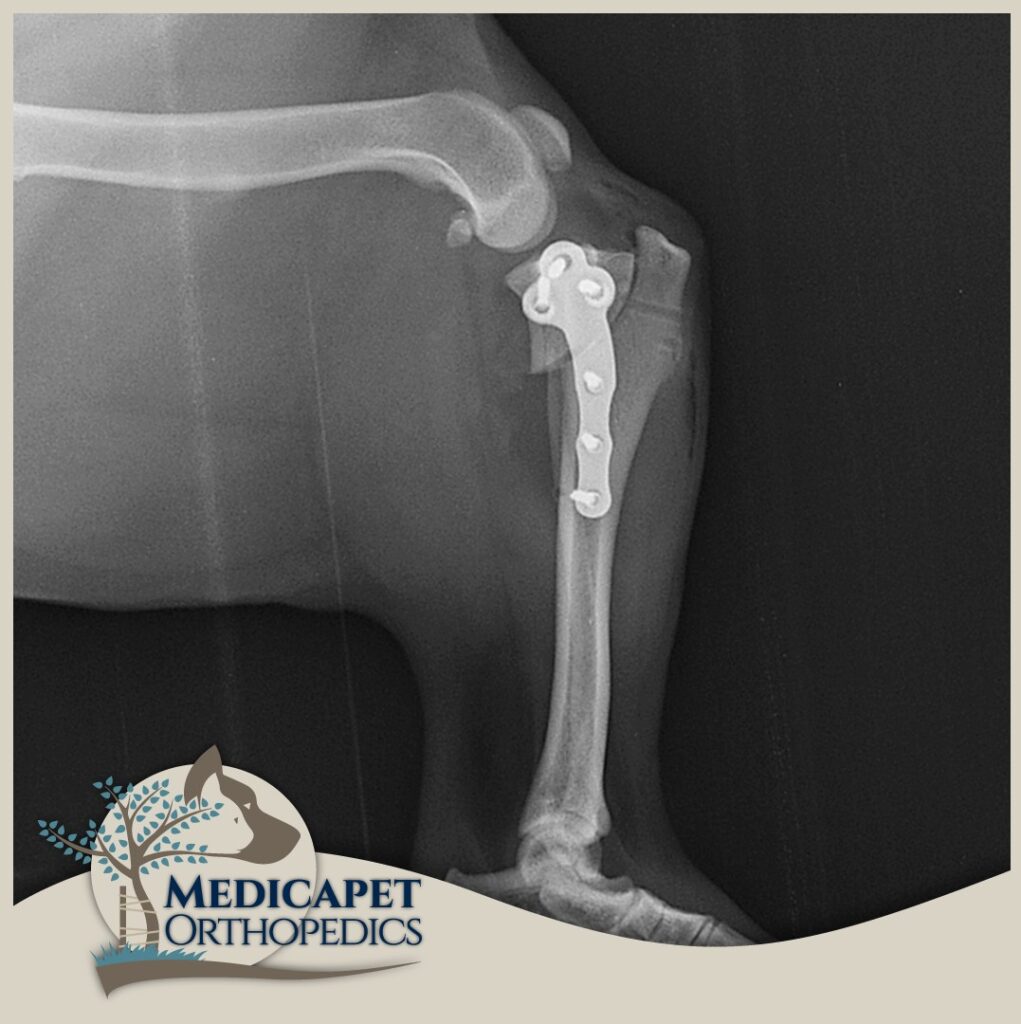

TPLO – Tibial plato seviyeleme osteotomisi

Bu ameliyat, tibianın üst kısmında dairesel bir kesi oluşturulmasını ve kemikteki önceki eğim artık mevcut olmayana kadar plato segmentinin döndürülmesini içerir. Daha sonra kemik, kemik plakası ve vidalar kullanılarak bu yeni pozisyonda sabitlenir. Böylece femurun tibia üzerinde uygunsuz şekilde kayması engellenmiş olur. Hassas ölçümler ve kusursuz el maniplasyonu gerektirdiği için tecrübeli ve ehil cerrahlar tarafından uygulanmalıdır.

Kemik iyileşmesinin bağ iyileşmesinden daha kolay ve hızlı olması sebebiyle, bu onarımlar hasarlı bağın değiştirilmesi için tasarlanan ameliyatlardan önemli ölçüde daha sağlamdır. En büyük pratik fayda, tüm köpeklerin kısa süre içinde ameliyat edilen uzuvda ağırlık taşımaya başlamasının beklenmesiyle, uzuv kullanımının çok güvenilir bir şekilde geri dönmesidir. TPLO ve TTA’nın mekanik avantajları, hızlı işleve dönüşle birleştiğinde, özellikle ağır köpekler, atletik hayvanlar, hafif aksama gösteren hayvanlar ve her iki diz eklemini de etkileyen ön çapraz bağ yaralanmaları olan hayvanlar için önemlidir. Her iki dizini aynı anda etkileyen ön çapraz bağ yaralanmaları olan bazı hayvanlarda, TPLO tek bir ameliyatta her iki diz eklemine uygulanabilir. Bağ değiştirme teknikleri kullanıldığında bu mümkün değildir.